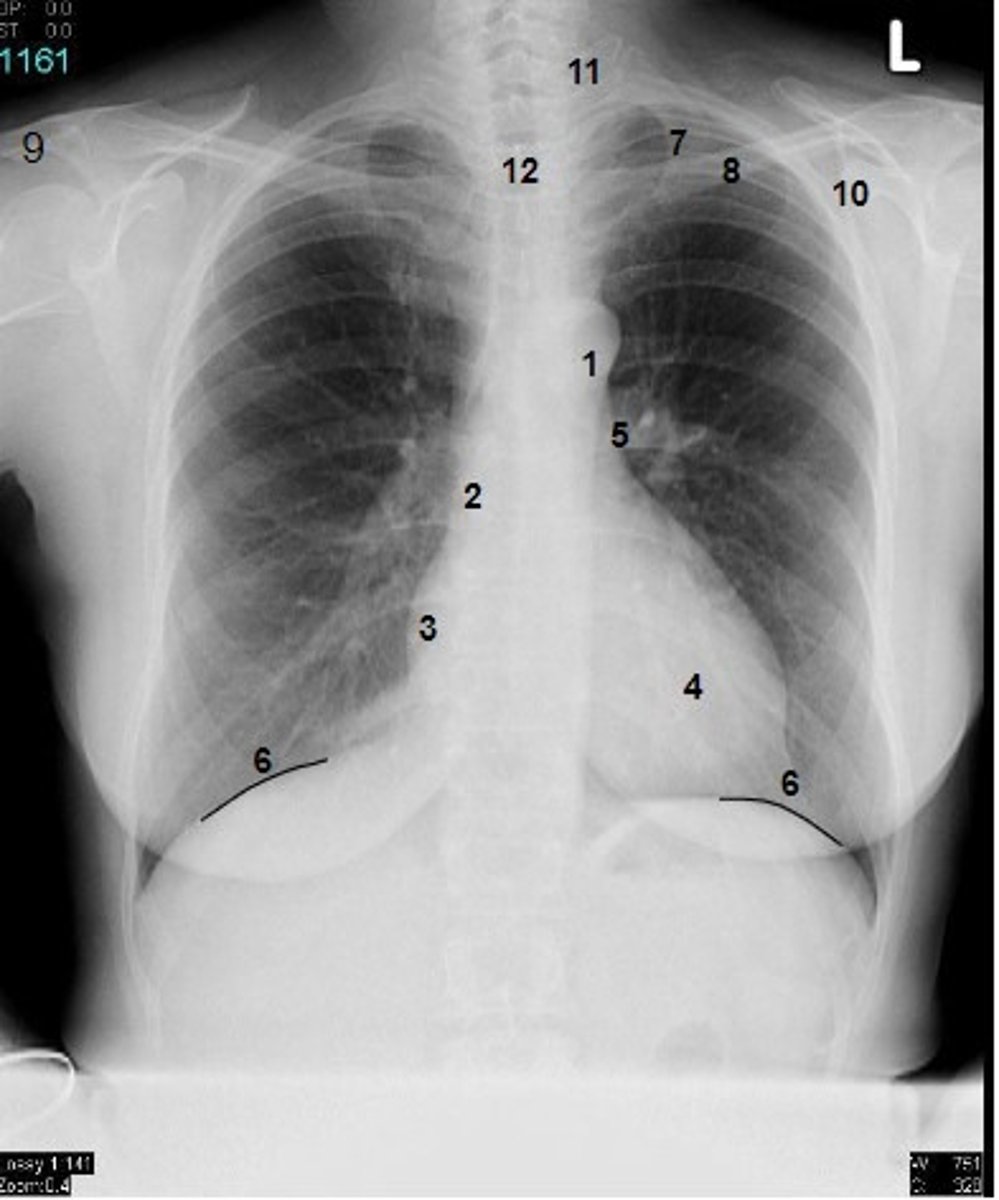

1

at what number is the arch of aorta?

2

at what number is the superior vena cava

3

at what number is the right atrium

4

at what number is the left ventricle

5

at what number is the primary bronchus

6

at what number is the dome of diaphragm

7

at what number is the first rib

8

at what number is the clavicle

9

at what number is the acromion of scapula

10

at what number is the coracoid process of scapula

11

at what number is the transverse process of vertebra

12

at what number is the spinous process of vertebra